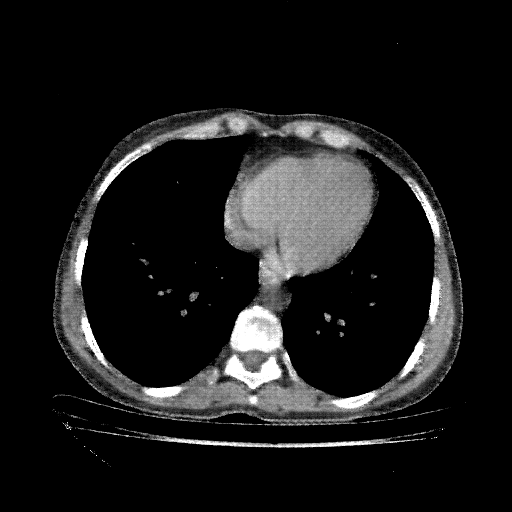

Generated VENOUS CT scan (A→B translation)

Full window (WL 1023.5, WW 4095 β†’ Low βˆ’1024, High +3071)

Actual HU range: [-1024.0, 959.4]

Lung window (WL -600, WW 1500 β†’ Low βˆ’1350, High +150)

Actual HU range: [-1350.0, 150.0]

Mediastinum window (WL 40, WW 400 β†’ Low βˆ’160, High +240)

Actual HU range: [-160.0, 240.0]